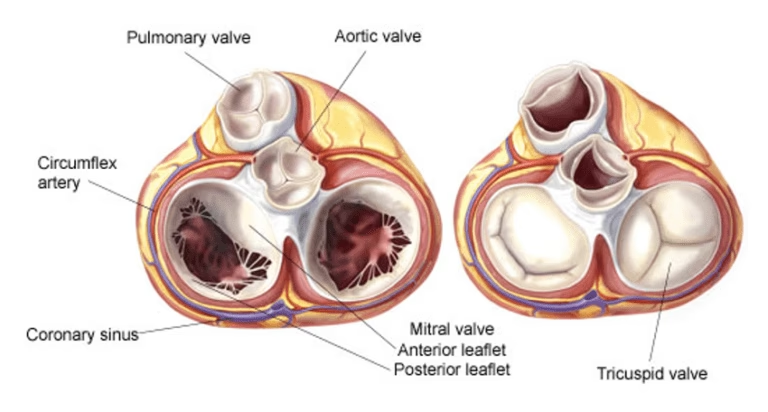

La válvula mitral es una de las cuatro válvulas del corazón y su función es crucial para garantizar que la sangre fluya en la dirección correcta, desde la aurícula izquierda hacia el ventrículo izquierdo. Cuando esta válvula no funciona adecuadamente, ya sea porque no cierra bien (regurgitación o insuficiencia) o porque no abre completamente (estenosis), puede generar serios problemas de salud. La cirugía de la válvula mitral se ha convertido en una solución eficaz y segura para corregir estos defectos, pero una de las preguntas más importantes tanto para pacientes como para médicos es: ¿cuál es el momento exacto para intervenir? Este artículo profundiza en las indicaciones, tipos de procedimientos y los factores clave que determinan cuándo es necesaria la cirugía de la válvula mitral.

Antes de hablar de cirugía, es fundamental comprender las dos principales afecciones que pueden requerir una intervención:

Una vez que se decide operar, la siguiente gran pregunta es si se debe reparar la válvula existente o reemplazarla por una prótesis. La evidencia científica es contundente: la reparación valvular es preferible al reemplazo siempre que sea técnicamente posible (Recomendación Clase I).

La reparación es especialmente exitosa en la enfermedad degenerativa (prolapso), donde cirujanos expertos pueden alcanzar tasas de éxito superiores al 95%.

El reemplazo se reserva para los casos en que la válvula está demasiado dañada para ser reparada de forma duradera. Esto suele ocurrir en casos de enfermedad reumática avanzada con mucha calcificación o en infecciones que han destruido gran parte del tejido valvular.